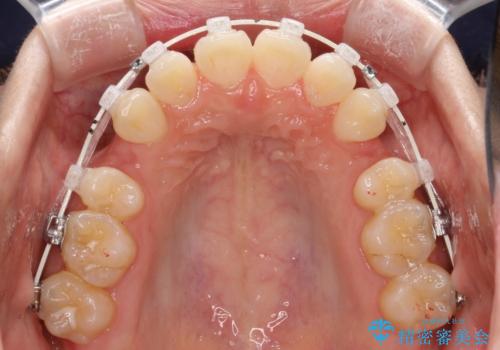

- 矯正装置

- 審美装置

- 前歯の凸凹を主訴に来院されました。

小臼歯抜歯(上顎4番)して矯正治療を行なったことで、口元もスッキリしました。